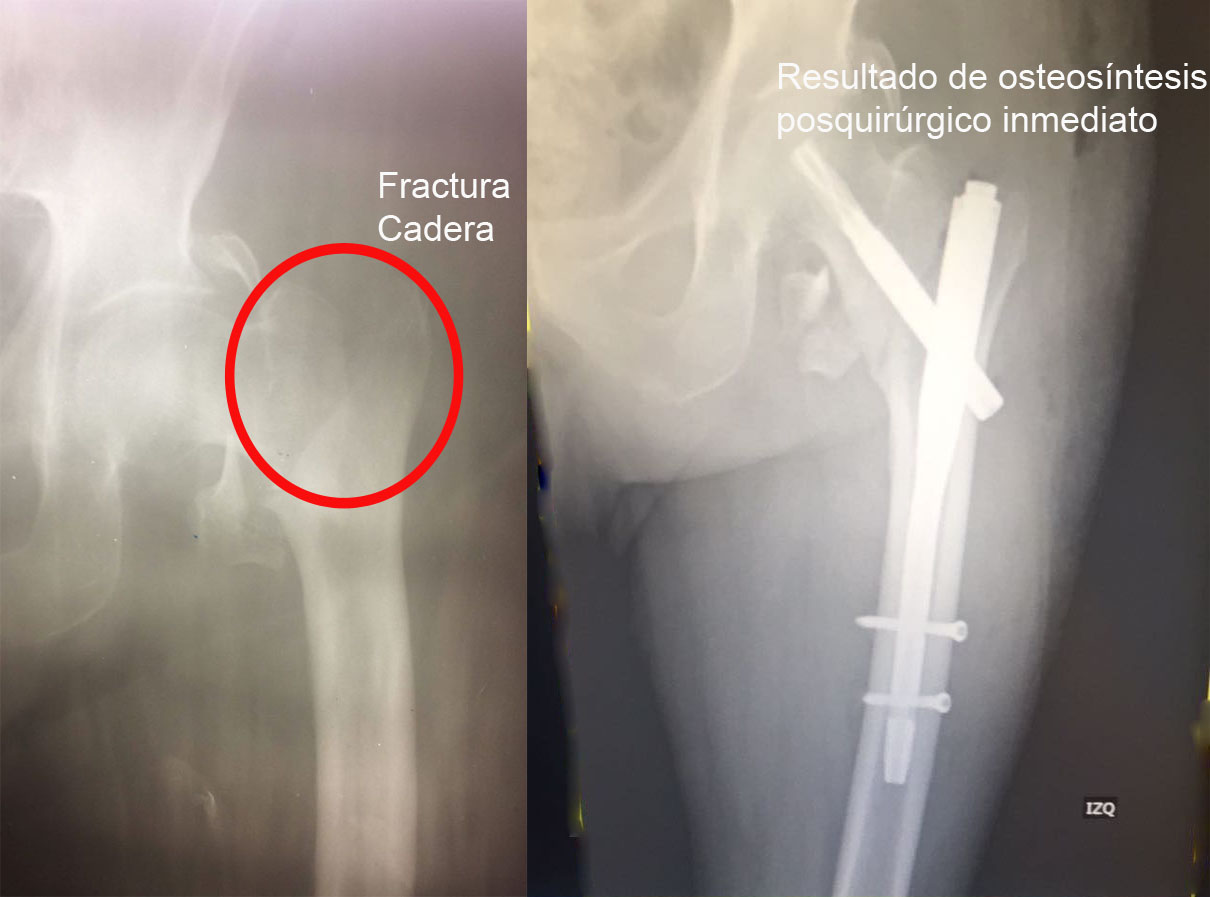

Una fractura ósea es la ruptura de un hueso, la cual puede presentarse por diversas causas y su tratamiento dependerá de la magnitud, sitio anatómico y de las enfermedades concomitantes. Algunas pueden manejarse de forma conservadora con solo inmovilización y hay otras que requieren de un tratamiento quirúrgico. A continuación, podrá ver algunos casos quirúrgicos, dando clic a la zona del cuerpo afectada.